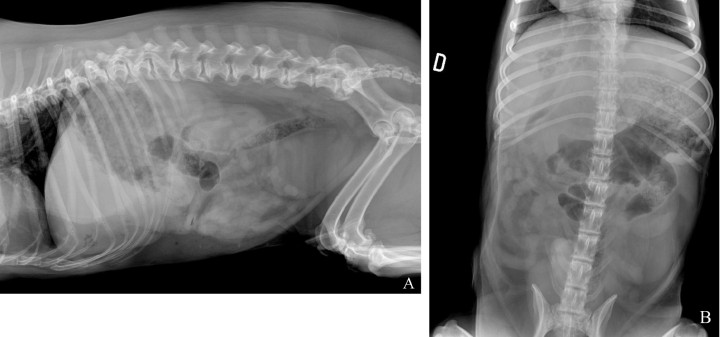

Se realizó un estudio radiográfico de abdomen con proyecciones lateral izquierda y ventrodorsal (Fig. 1).

<p>Radiografías de abdomen de un perro mestizo de 12 años en proyección lateral izquierda (<strong>A</strong>) y proyección ventrodorsal (<strong>B</strong>).</p>

Radiografías de abdomen de un perro mestizo de 12 años en proyección lateral izquierda (A) y proyección ventrodorsal (B).

Se observa una disminución de la visualización de las serosas abdominales en el abdomen craneal y medio (Fig. 2), con presencia de pequeñas burbujas de gas libre caudoventral a la silueta hepática compatible con neumoperitoneo (Fig. 2A). Ambas proyecciones mostraban una hepatomegalia con bordes redondeados excediendo levemente el arco costal, con presencia de una zona de opacidad gas, de morfología y bordes irregulares, poco definidos, localizada en la zona de proyección hepática en su aspecto craneoventral y con lateralización hacia la derecha (Fig. 2). Así mismo, se apreció otra lesión, de opacidad gas y de menor tamaño, caudalmente a la previamente descrita, en la zona media del hígado y asociada a un efecto masa en la proyección ventrodorsal, que producía hacia caudal un desplazamiento del cuerpo gástrico y antro pilórico (Fig. 2B). Como hallazgo incidental, se observó una espondilosis ventrolateral deformante en la columna lumbar.

Las radiografías del abdomen pueden mostrar hepatomegalia, pero rara vez se aprecia una masa bien definida.[ Welch Fossum, T. Cirugía del hígado. En: Welch Fossum T. 3ª ed. Cirugía en pequeños animales. Barcelona, España: Elsevier; 2009; 531-559. ] Cuando el absceso esté producido por bacterias productoras de gas, superpuesto con el parénquima hepático, el gas se podrá visualizar como un patrón moteado e irregular, normalmente en un área localizada.[ Larson MM. Liver and spleen. En: Thrall DE, 7th ed. Textbook of Veterinary Diagnostic Radiology. St. Louis, MO: Elsevier; 2018; 792-822 ]